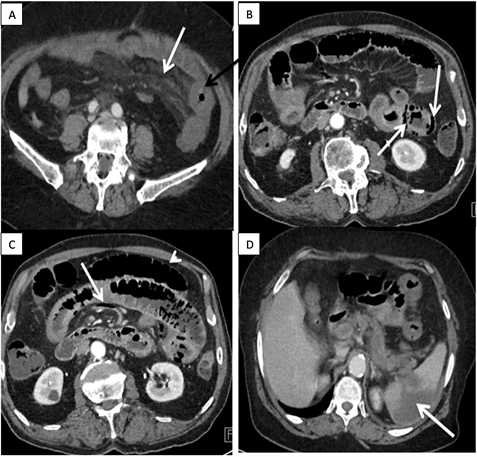

Serious symptoms are represented in Table 1: Sixteen patients were having serious symptoms. There was intraabdominal fluid effusion in 13 cases, parietal pneumatosis in 06 (Figure 2(B)), aeromesentery in 02 cases (Figure 2(C)), hepatic portal venous gas in 01 case, parietal tightening in 02 cases (Figure 2(C)), pneumoperitoneum in one case and intestinal distention in 03 cases (Figure 2(C)).

The vascular lesions are distributed in Table 2: We noted 16 cases of mesenteric ischemia and 04 cases of ischemic colitis. The mesenteric ischemia was arterial in 75%, venous in 12% and mixed in 12% of cases. Partial or total occlusion of the upper mesenteric artery (UMA) was noted in 10 cases (Figure 3(A)-(C)). Occlusion of the portal vein was noted in 03 cases (Figure 3(D)) and upper mesenteric vein (UMV) occlusion in 03 cases (Figure 3(C) and Figure 3(D)). In 07 cases, no vascular occlusion was viewed. Diffuse atherosclerosis was revealed in 09 cases (Figure 3(B)) and 01 case of left intraventricular embolism was found.

Figure 2. Abdominal angioscan with injection of contrast dye in portal phases, axial sections. (A) Thickening with lack of heightening of the left colonic lining (black arrow); mesenteric infiltration (white arrow); (B) Aeromesentery (white arrow), parietal tightening with intestinal distention (head of white arrow); (C) Parietalpneumatosis (white arrows); (D) Splenic infarction (white arrows).

Figure 3. Abdominal angioscan with injection of contrast dye, in arterial phase in sagittal MIP reconstruction (A & B); coronal MIP reconstitution in portal phase (C & D). (A) Total obstruction of the celiac trunk (white arrow), total obstruction of the upper mesenteric artery (black arrow); (B) Stenosis of the upper mesenteric artery at 70% in its beginning by a plaque of calcified atheromas (white arrow), diffuse atheromatous infiltration of the abdominal aorta; (C) Mixed obstruction of the upper mesenteric artery (black arrow) and the upper mesenteric vein (white arrow); (D) Total obstruction of the mesenteric-portal venous axis (white arrow), intraabdominal fluid effusion (black arrow).